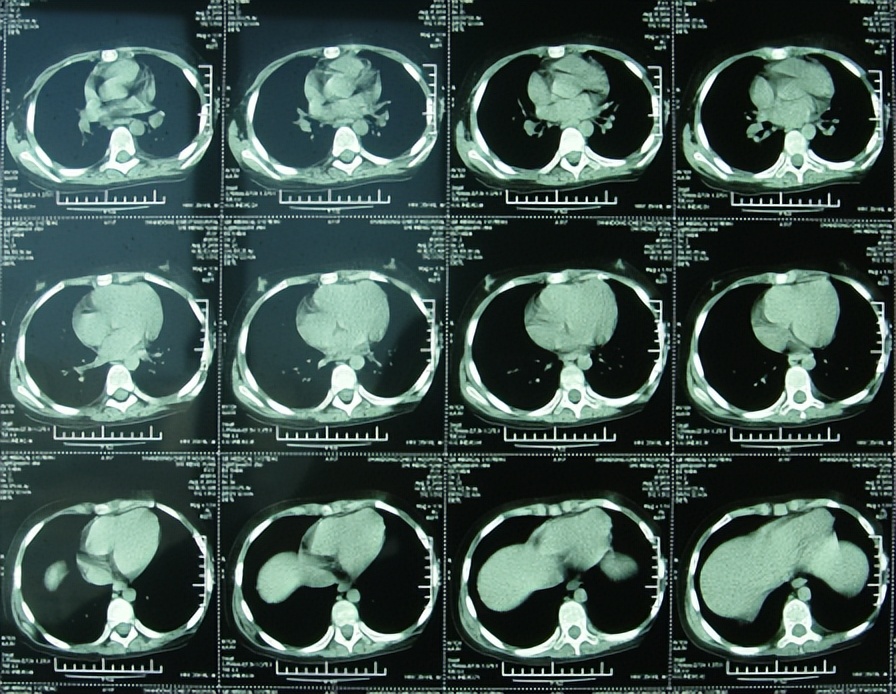

在2010年5月23日(发病后17天)转入小儿神经内科后,腰穿脑脊液检查的结果提示白细胞数显著增多,达到>2000的严重程度,进一步查头颅核磁(图-1)后,诊断为“化脓性脑膜炎”,抗感染治疗(万古霉素,美罗培南等)治疗18天。

图-1:2010年5月23日头颅核磁